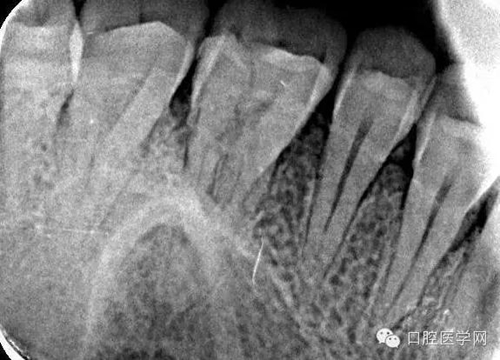

26根尖片可見低密度暗影:

二次復(fù)診患者訴36疼,根尖片未見異常。